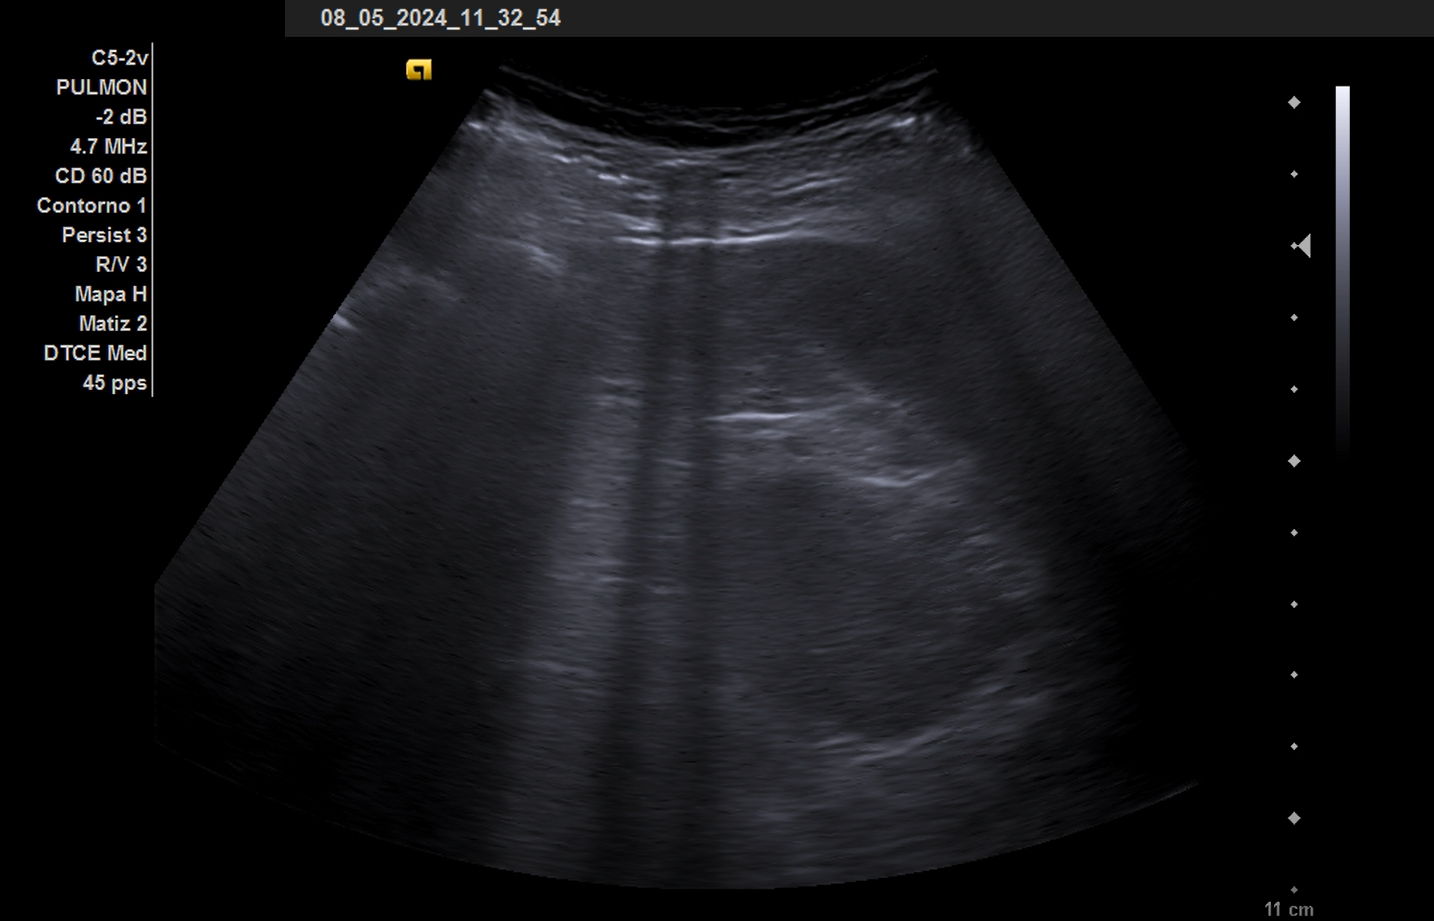

La ecografía pulmonar se ha realizado en el seguimiento.

El abordaje clínico es la base de la atención al paciente. Como complemento a la exploración física se debe practicar una ecografía, en este caso pulmonar donde se visualizan Líneas E, que se inician desde piel a diferencia de las líneas B que se inician desde línea pleural. En el caso en cuestión la ecografía ha complementado el seguimiento desapareciendo dichos hallazgos al mes.